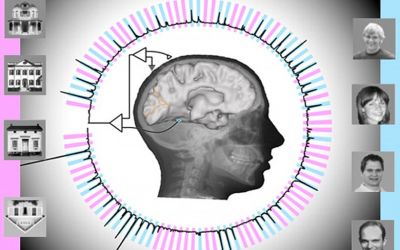

গবেষকরা দাবি করেছেন, নতুন একটি কম্পিউটার প্রোগ্রাম প্রায় কাছাকাছি সময়েই মানুষের চিন্তাকে বুঝতে পারবে। মানুষের মস্তিষ্কে বসানো ইলেকট্রোড থেকে আসা বৈদ্যুতিক সংকেতের ওপর ভিত্তি করে তারা জানতে পেরেছে মানুষ কী ভাবছে। এই পদ্ধতি ব্যবহার করে মস্তিষ্ক অকার্যকর হওয়া রোগীদের চিন্তা ভাবনা জানা যাবে।

গবেষকরা জানান, নতুন কম্পিউটার প্রোগ্রাম ব্যবহার করে দেখা গেছে, মানুষকে একটি ছবি দেখানোর মিলিসেকেন্ডের মধ্যে তার মস্তিষ্কের সঙ্গে কম্পিউটারের সংযোগ ঘটেছে, যা কিনা ৯৫ শতাংশই সঠিক বলে আমাদের কাছে মনে হয়েছে।

গবেষকরা লাইফ সার্পোটে থাকা রোগীদের জাগ্রত করতে ইলেকট্রোড পদ্ধতি ব্যবহার করেন। উপরন্তু, চাক্ষুষ উদ্দীপনার জন্য দুই শ্রেণীর রোগীদের নিউরাল প্রতিক্রিয়া বিশ্লেষণ করে মুখ ও ঘর ইমেজ দেখে রোগীরা কি ভাবছেন বা দেখছেন তা পরবর্তীকালে বিজ্ঞানীরা জানতে পেরেছেন এবং এই প্রক্রিয়াটি ছিল ৯৫ শতাংশ সঠিক।